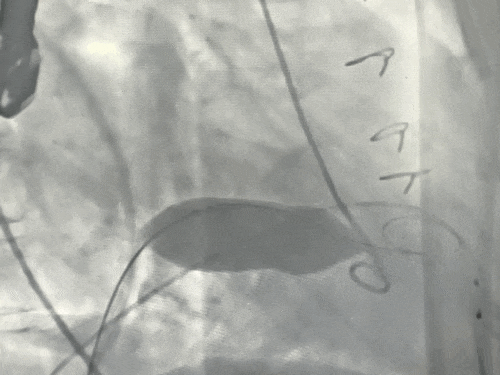

球囊预扩张同时行左室造影评估

经左股动脉送入猪尾导管至左心室。在快速心室起搏下,使用14×40 mm球囊对衰败的二尖瓣生物瓣进行预扩张,同期行左室造影评估,判断新瓣膜植入后发生左室流出道梗阻的风险较低。